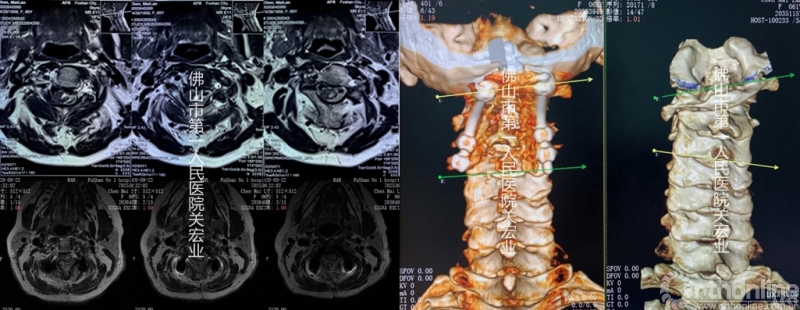

影像学检查:

术前放射检查

术前CT

术前CTA

术前MR

影像学术前、术后对比